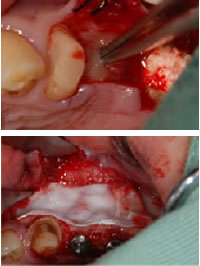

4.再生治療

できたフィブリンゲルは、再生治療に使用します。骨を作製したい部分に埋入(上の写真)したり、平たくつぶしてメンブレンとして使用(下の写真)したりします。 メンブレンとは歯槽骨を造成するための膜のことです。 ※症例によっては人工の吸収性メンブレンを使用する場合もございます。